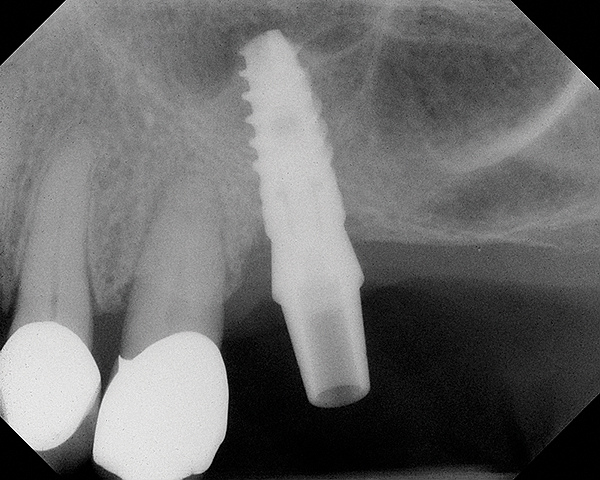

The implant is then delivered and should be well stabilized in the bone. If there is any mobility of the implant, it can either be placed a little deeper (if there is enough native bone) or the implant can be removed and the procedure aborted, in which case it would be a two-stage procedure. This should rarely occur with the tapered designed implant, even with only 2 mm of native bone. Using a bone-level platform-shifting implant (or a tissue-level designed implant) is critical, as the hard and soft tissue will establish a biologic width. If an external hex type of implant is used and the shoulder is placed at the bone level, an expected bone loss of 1.5 mm to 2 mm will occur.24 Figure 10 shows proper bone-level implant depth placement with a platform-shifting design. In this case, a 3-mm healing abutment was placed at the time of surgery to avoid a secondary uncovering surgery, but an implant-level healing abutment could have been placed instead. As can be seen, there was only about 2 mm to 3 mm of native bone height. The membrane was raised about 8 mm to 9 mm. Comparing the radiograph on the day of surgery (Figure 10) to the 6-month postoperative radiograph (Figure 11) shows no loss of native bone, as well as the positive change in appearance of the grafted bone. The 3.5-month CBCT scan (Figure 12) shows good healing of the bone with no coronal bone loss. With minimal native bone present, as in this case, the use of a non-platform-shifting or non-tissue-level implant design could be problematic. After 1.5 mm to 2 mm of crestal bone loss, an external hex designed implant could develop instability with possible implant failure. If a non-tapered implant is used and bone loss occurs during healing, migration of the implant into the sinus could potentially occur. The surgeon can use either a healing abutment or implant-level closure screw over the implant shoulder. With patients who tend to use their tongues to explore or play with the area, or if the area is under a removable partial denture, a closure screw is recommended.

Fig 10. Radiograph of implant No. 3 and sinus augmentation, day of placement. There is about 2 mm to 3 mm of native bone, and the sinus has been raised about 8 mm to 9 mm.

Figure 10

Fig 11. 7-month postoperative radiograph of the restored implant No. 3.

Figure 11

Fig 12. CBCT scan (Kodak 9000D) showing 3.5-month postoperative of implant No. 3 in place. Note homogenous appearance of the bone.

Figure 12